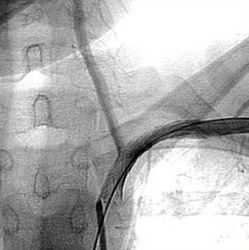

В первую очередь пытаются произвести эндартерэктомию. Для этой цели из левосторонней передне-боковой торакотомии подходят, по описанному выше способу, к этим сосудам, выделяют их и берут на турникет. Устье этих сосудов в области аорты выделяется вместе с соответствующим участком дуги аорты, чтобы можно было произвести отжатие небольшого участка стенки аорты. Одновременно выбирают нужный сосудистый зажим и накладывают его провизорно. Первые ветвц подключичной артерии, внутренняя грудная артерия, щитовидно-шейный ствои позвоночная артерия выделяются и берутся на турникет.

После наложения пристеночного зажима на дугу аорты в области устья оперируемого сосуда производят артериотомию, переходящую немного на стенку аорты. В необходимом для этого слое производят эндартерэктомию и при показаниях фиксируют отслоившуюся дистальную часть ин-тимы. Артериотомическое отверстие закрывается по возможности непрерывным швом, и только в случае возможного сужения просвета сосуда применяется пластика синтетической заплатой. Важным моментом является удаление всего воздуха из реканализированного сосуда, так как попадание пузырьков воздуха через позвоночную артерию может вызвать эмболию сосудов головного мозга. Поэтому снятие зажимов с позвоночной артерии производится в последнюю очередь, после того, как в течение 2—3 минут восстановлено кровообращение в сосудах верхней конечности. В тех случаях, когда эндартерэктомия не может быть произведена, из того же доступа накладывают шунт между аортой и подключичной артерией. Протез вшивают на границе между дугой аорты и нисходящей ее частью.